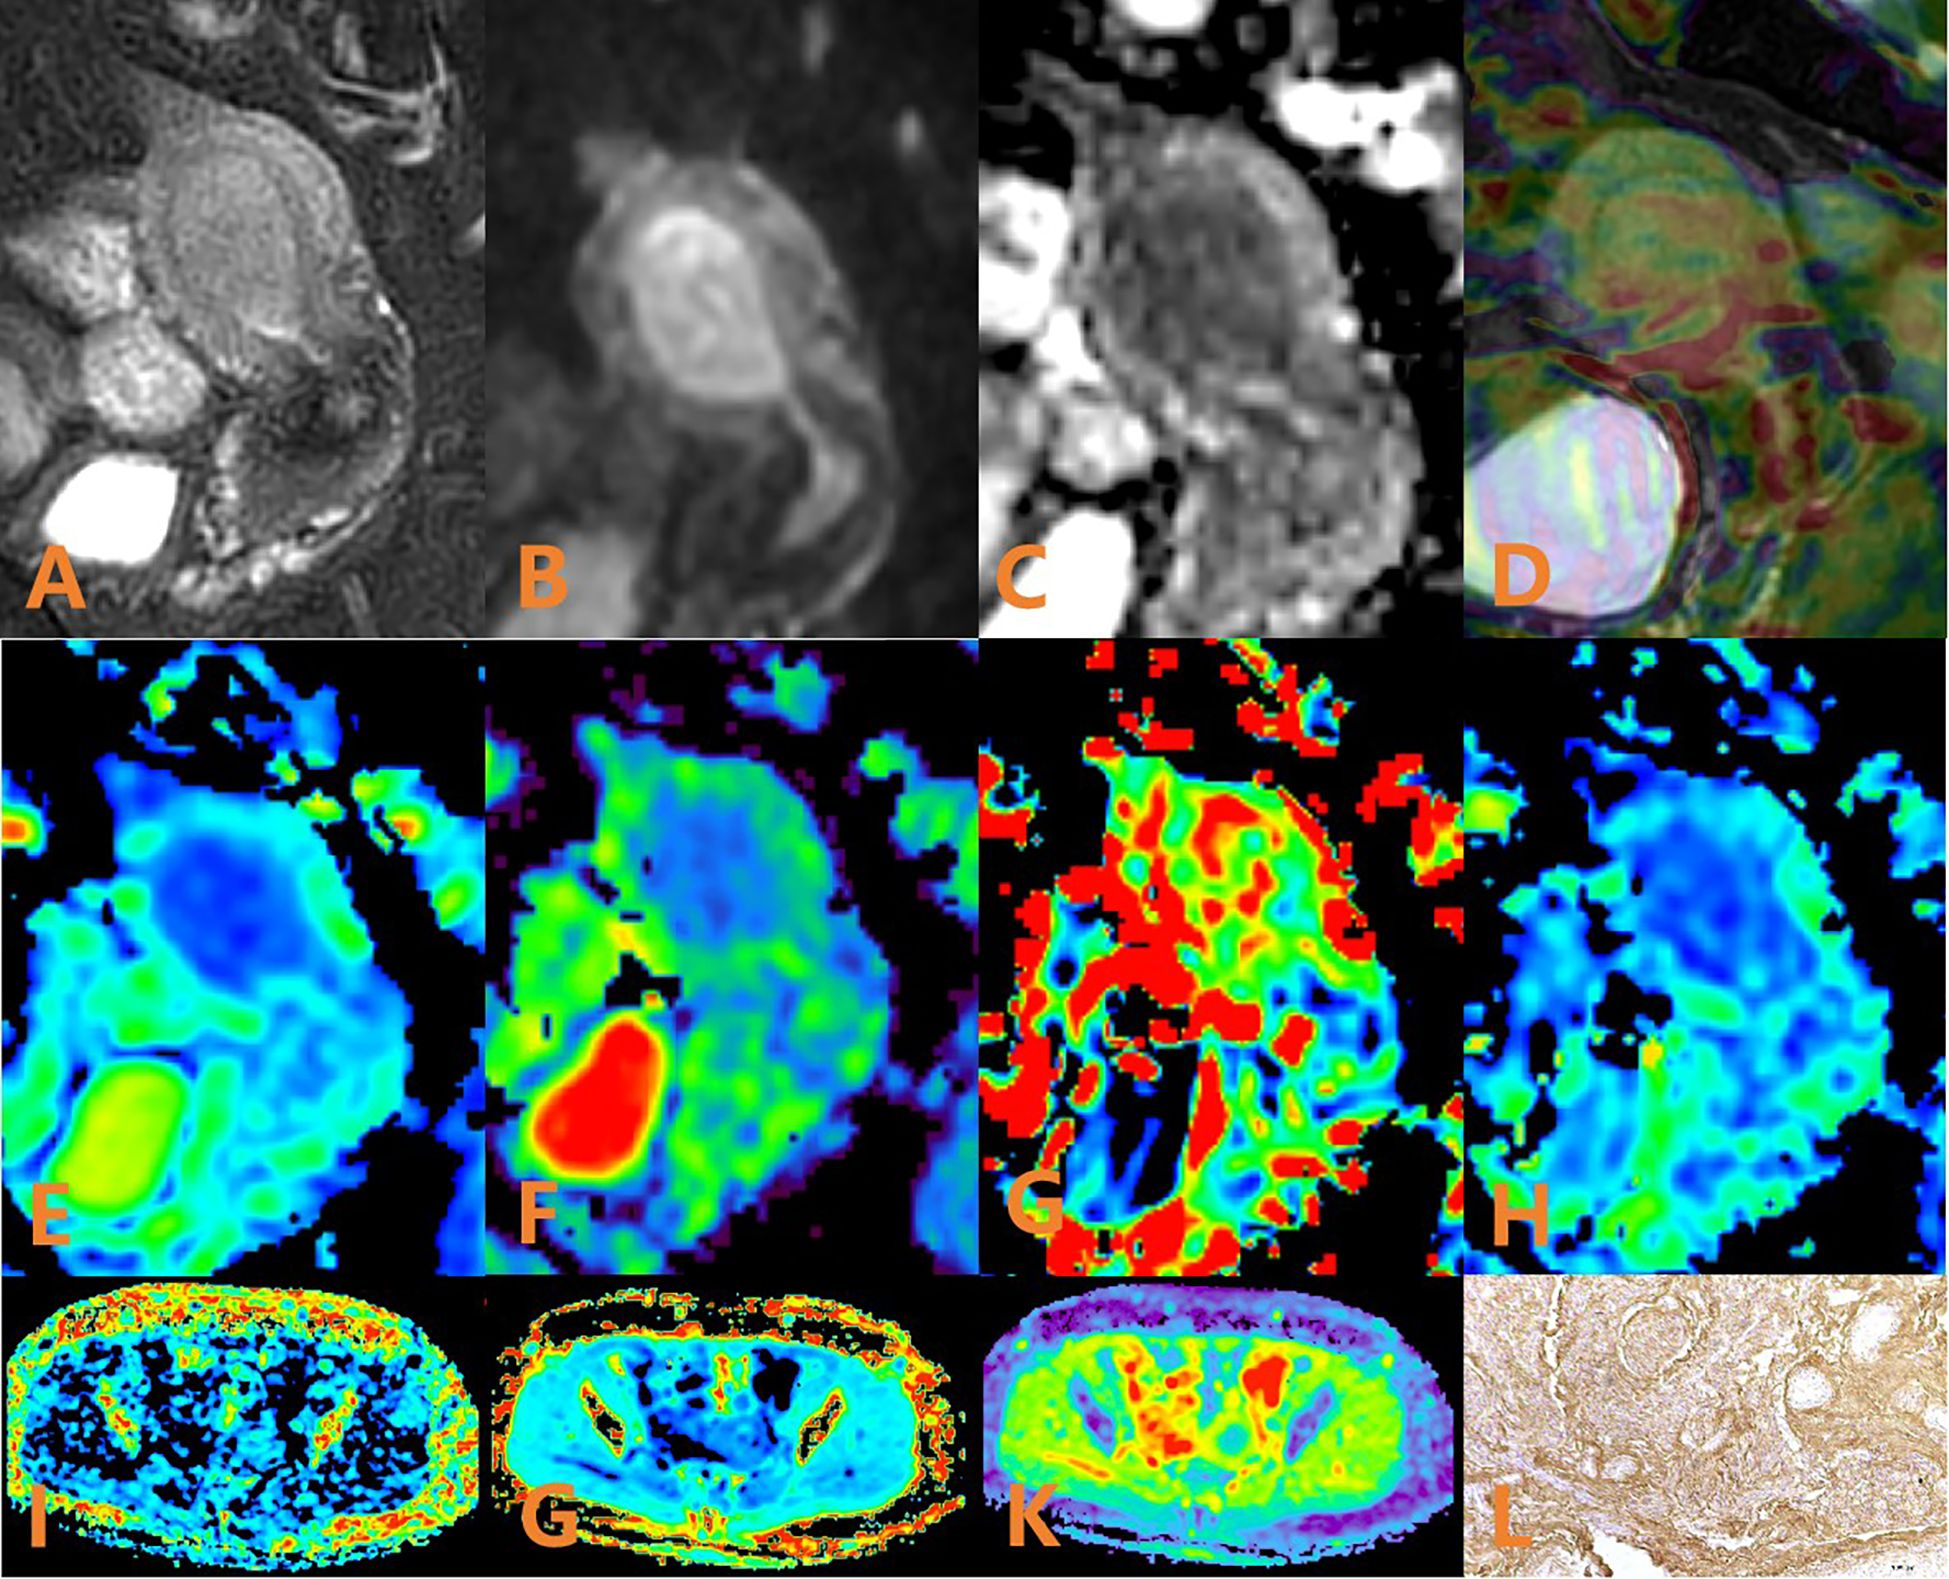

Figure 2. APTw, DKI and IVIM parameters for an EC patient with low HIF-1α expression. (A) sagittal T2WI, showing a slightly high signal mass in the uterine cavity; (B) sagittal DWI image; (C) sagittal ADC image; (D) APTw fused with T2WI (mean MTRasym value 3.53%); (E–H) ADC, D, D*, and f images. Mean values are 0.600 × 10–3 mm2/sec for ADC, 0.410 × 10–3 mm2/sec for D, 0.280 × 10–2 mm2/sec for D* and 0.57% for f; (I–K) FA, MK, and MD images. Mean values are 0.388 for FA, 0.586 for MK, and 1.147 μm2/ms for MD; (L) Immunohistochemical staining image (×200) showed that HIF-1α expression of the tumor appeared as low expression.